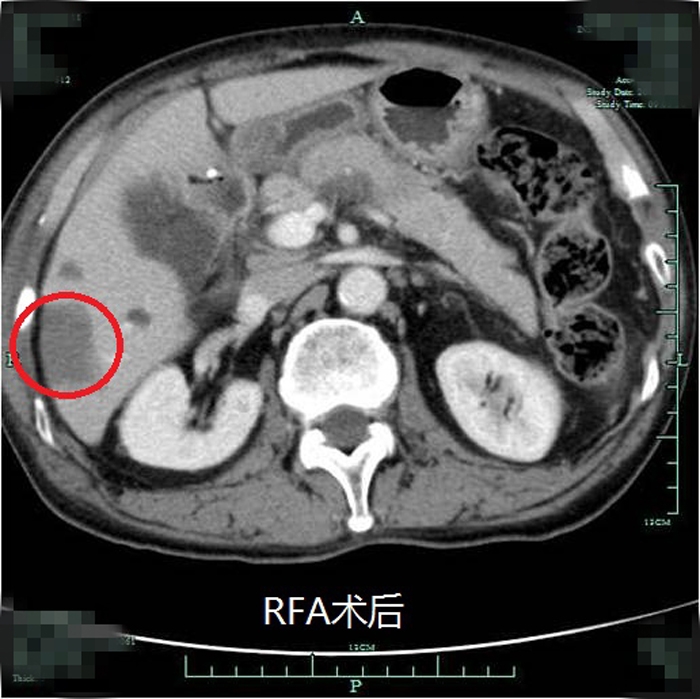

典型射頻治療患者術(shù)前術(shù)后效果對比(非該尾狀葉患者)